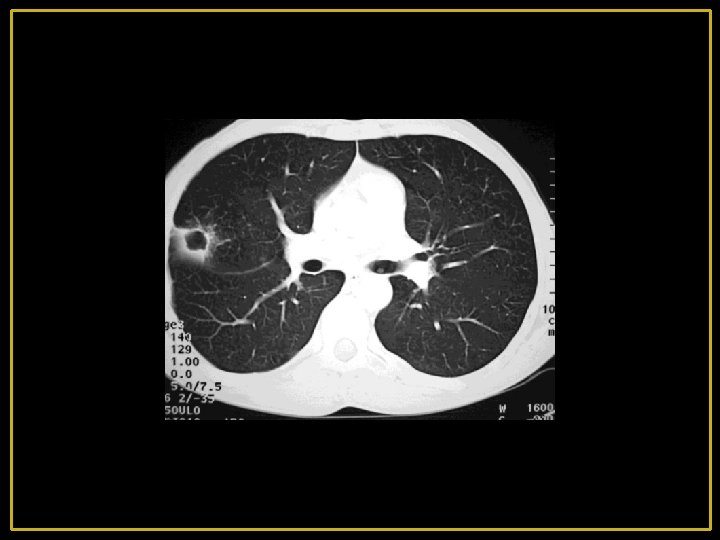

4 -Radiologie : - Distension thoracique majeure avec hyper clarté pulmonaire diffuse par raréfaction de la trame vasculaire. - L'existence parfois des bulles d'emphysème siégeant aux lobes inférieurs - Le cœur est petit, allongé, décollé de la coupole dit en « goutte » .

4’-Radiologie: -Distension thoracique modérée -Signes d'inflammation bronchique et pulmonaire prédominant aux bases. -Hyperclarté des sommets. -Cardiomégalie par retentissement pulmonaire CPC -Artères pulmonaires dilatées.